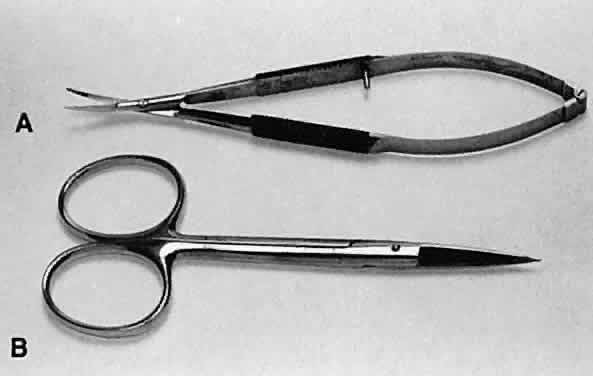

Scissors can be used in three ways to cut tissue: closing the blades, opening

the blades, and advancing the tips of the blades. Two basic types

of scissors are used in ophthalmic surgery: scissors with ringed handles

and a simple screw joint, and scissors with a spring handle (Fig. 23). The blades of the scissors may be straight or curved. The ability of

as the cornea and sclera.  Fig. 23. Two types of scissors are used for most ophthalmic surgery. A. Spring-handle scissors. B. Ring-handle scissors with a simple screw joint. The blades may be straight

or curved, and the scissors may be used for blunt or sharp dissection. Fig. 23. Two types of scissors are used for most ophthalmic surgery. A. Spring-handle scissors. B. Ring-handle scissors with a simple screw joint. The blades may be straight

or curved, and the scissors may be used for blunt or sharp dissection.